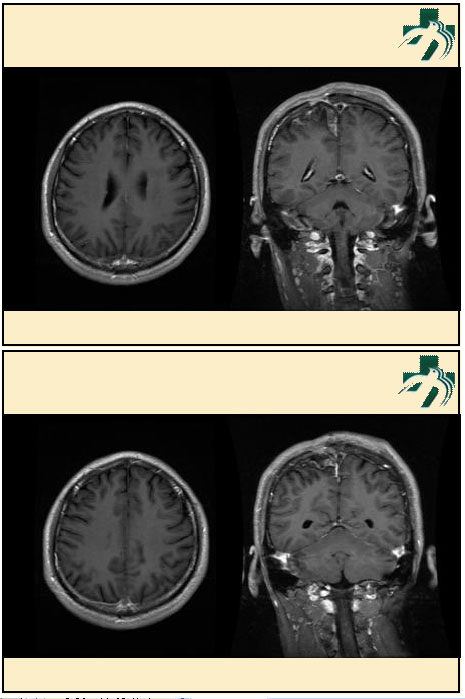

奴卡氏菌感染

第九期三博

读片会

病例之四

北京协和医院 提供

男性,22岁。自觉虫咬后皮疹、肢体麻木4月